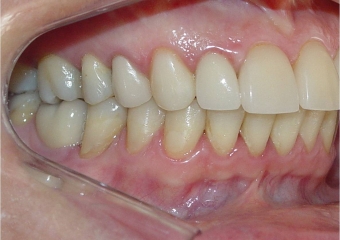

Mordida perfil final